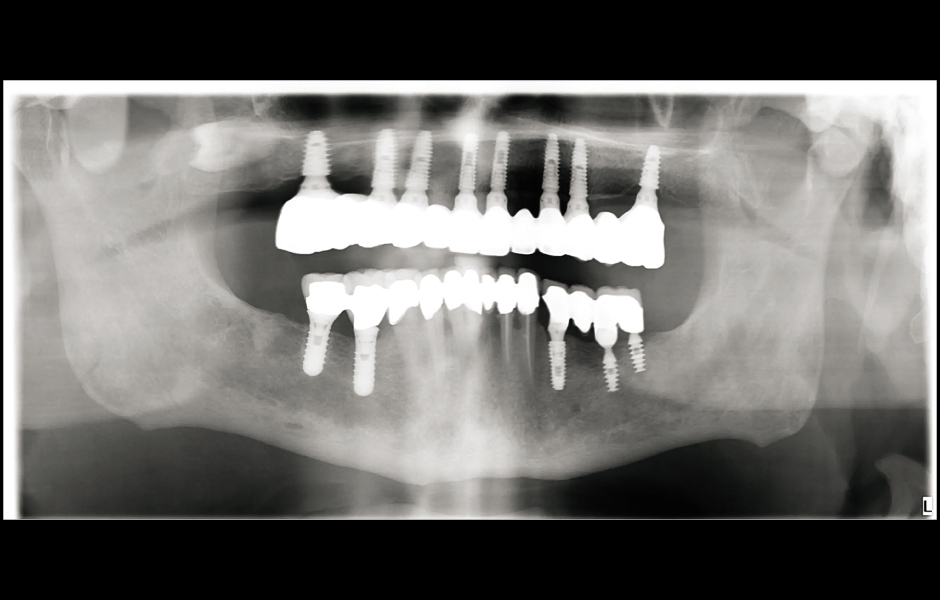

Obr. 22: Panoramatický rentgenový snímek chrupu po jednom roce.

Při finální návštěvě byla nasazena definitivní hybridní šroubem fixovaná protetika. Definitivní práce sestávala z CAD/CAM titanového skeletu přišroubovaného na všechny implantáty a tří monolitických zirkoniových segmentů vlepených nahoře (obr. 18a–c). Byla zkontrolována okluze a pacient byl zařazen do čtyřměsíčního recall programu. Při poslední kontrole (rok po implantaci) byly všechny implantáty úspěšné a pacient byl plně spokojen s novou protetikou (obr. 19–22).